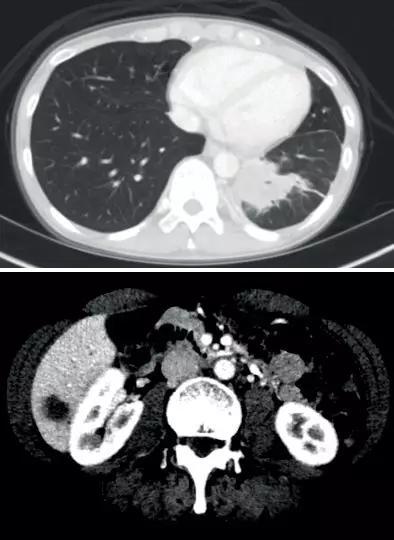

患者4:SQSTM1-NTRK1融合非小细胞肺癌的持久反应

45岁女性被诊断患有IV期NSCLC腺癌 , 肝脏和纵隔转移以及肥厚性骨关节病(HOA)症状 , 她曾接受过以前的铂类和培美曲塞治疗 。

基因检测发现 , NTRK融合基因 , 接受larotrectinib100 mg每日两次 , 出现快速反应 , 表现为第1周期(研究第8天)HOA症状 , 咳嗽和疲劳的改善以及第3周期完全没有咳嗽 。 第54天出现部分反应 。 反应持续时间> 12.88个月 。